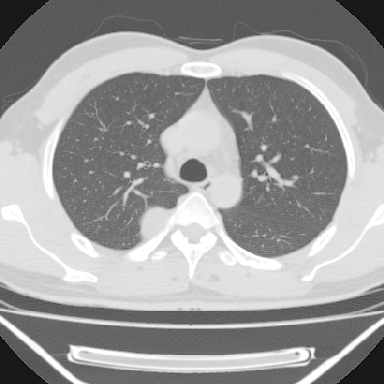

m 30 右胸痛10年

右上后纵隔脊柱旁类圆形肿块,边界光整,与胸腔呈钝角,首先考虑来源于肺外,神经源性肿瘤(神经鞘瘤可能大,神经鞘瘤)

右上后纵隔旁软组织肿块影,与肺界面光滑,与胸壁呈钝角相交,提示肺外病变。位于肋骨下缘,边缘清楚,呈三角样指向与右侧椎间孔,但并示进入椎间孔;与对侧神经根对比,属同一走行方向。

考虑后纵膈良性肿瘤,神经源性肿瘤可能大。

鉴别:胸膜来源肿瘤。影像表现虽有肺外征象,但无胸水等相应佐证;再者,病史前10年,超长,与胸膜肿瘤不太吻合。

建议:再次查体,问清疼痛部位,如为1~2个肋间痛则神经源性肿瘤可能大,如疼痛较弥散,不按肋间分布,则可能为后纵膈其它来源肿瘤。

右上后纵隔脊柱旁类圆形肿块,边界光整,与胸腔呈钝角,首先考虑来源于纵膈,神经源性肿瘤可能大。

右上后纵隔脊柱旁见长椭圆形肿块,边界光整,与胸壁呈钝角。周围骨质未见异常。

考虑、1、后纵隔神经源性肿瘤;

2、不除外单发胸膜间皮瘤。